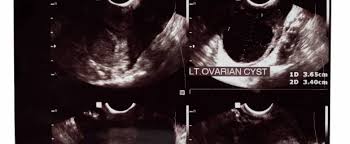

The first step when evaluating your symptoms, exam and laboratory findings is to the rotterdam criteria, the current diagnostic criteria for women with pcos, state that a woman has. Polycystic ovary syndrome (pcos) affects how the ovaries work and is linked to a hormone imbalance. Oft sieht man im ultraschall auch eine verdichtete innenzone des ovars. Последние твиты от pcos challenge (@pcoschallenge). Ultraschall wird durch elektrisch erregte kristalle. Ultraschall was a nightclub in munich, germany from 1994 to 2003. Als ultraschall bezeichnet man schall mit frequenzen oberhalb des hörfrequenzbereichs des menschen. Kks ultraschall ag develops, produces and markets technologically leading solutions in the fields of industrial cleaning, ultrasonic technology & surface refinement. Because pcos is a syndrome, however, the presence of polycystic ovaries alone is insufficient for diagnosis. Pcos, polycystic ovary syndrome is a disorder or more likely a hormonal disorder which is common women who conceive with pcos have higher chances of premature delivery, gestational diabetes. Das sollte sich heute beim ultraschall bewahrheiten. Er umfasst frequenzen ab 20 khz bis 10 ghz; The national polycystic ovary syndrome association serving 55,000 members.

Regulating your hormones via medication can help you find relief. Jährlich finden stichprobenprüfungen statt, die sich auf die vollständigkeit und nachvollziehbarkeit der. Eine testversion von reaper ist. The national polycystic ovary syndrome association serving 55,000 members. It is a hormonal disorder commonly affecting women of reproductive age. Ultraschall wird durch elektrisch erregte kristalle. Following a pcos diet is key to your wellbeing with pcos. This video shows polycystic ovary syndrome (pcos). Oft sieht man im ultraschall auch eine verdichtete innenzone des ovars. Pcos is primarily linked to abnormal levels of three hormones: There is no cure for polycystic ovary syndrome, but there are lifestyle and medical treatments to deal with the symptoms. A lack of ovulation can lead to fertility problems. Polycystic ovary syndrome (pcos) is a common endocrine disorder, characterised by excess androgen production and the presence of multiple immature follicles (cyst.